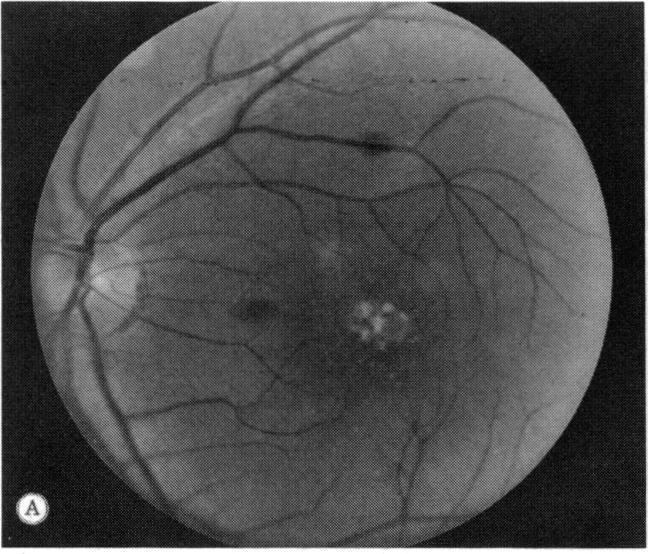

A family with a unique hereditary macular dystrophy is presented. The disorder is transmitted as an autosomal dominant trait having high penetrance and variable expression. The characteristics of this dystrophy are: childhood onset; nonprogressive areolar depigmentation of the central macula; and with the exception of one eye with a macular hemorrhage, normal vision acuity and retinal-function studies.

本文报告了一个患有独特遗传性黄斑营养不良的家族。该疾病以常染色体显性性状遗传,具有高外显率和可变表达。这种营养不良的特征为:儿童期发病;中央黄斑区出现非进行性乳晕色素脱失;除一只眼睛有黄斑出血外,视力和视网膜功能检查正常。